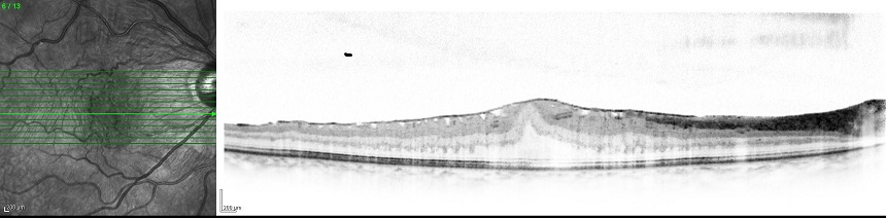

黄斑上膜(網膜前膜)に対する硝子体手術後のOCT画像、黄斑上膜は取り除かれ、網膜表面にしわが消失し、中心窩の凹みも回復している。